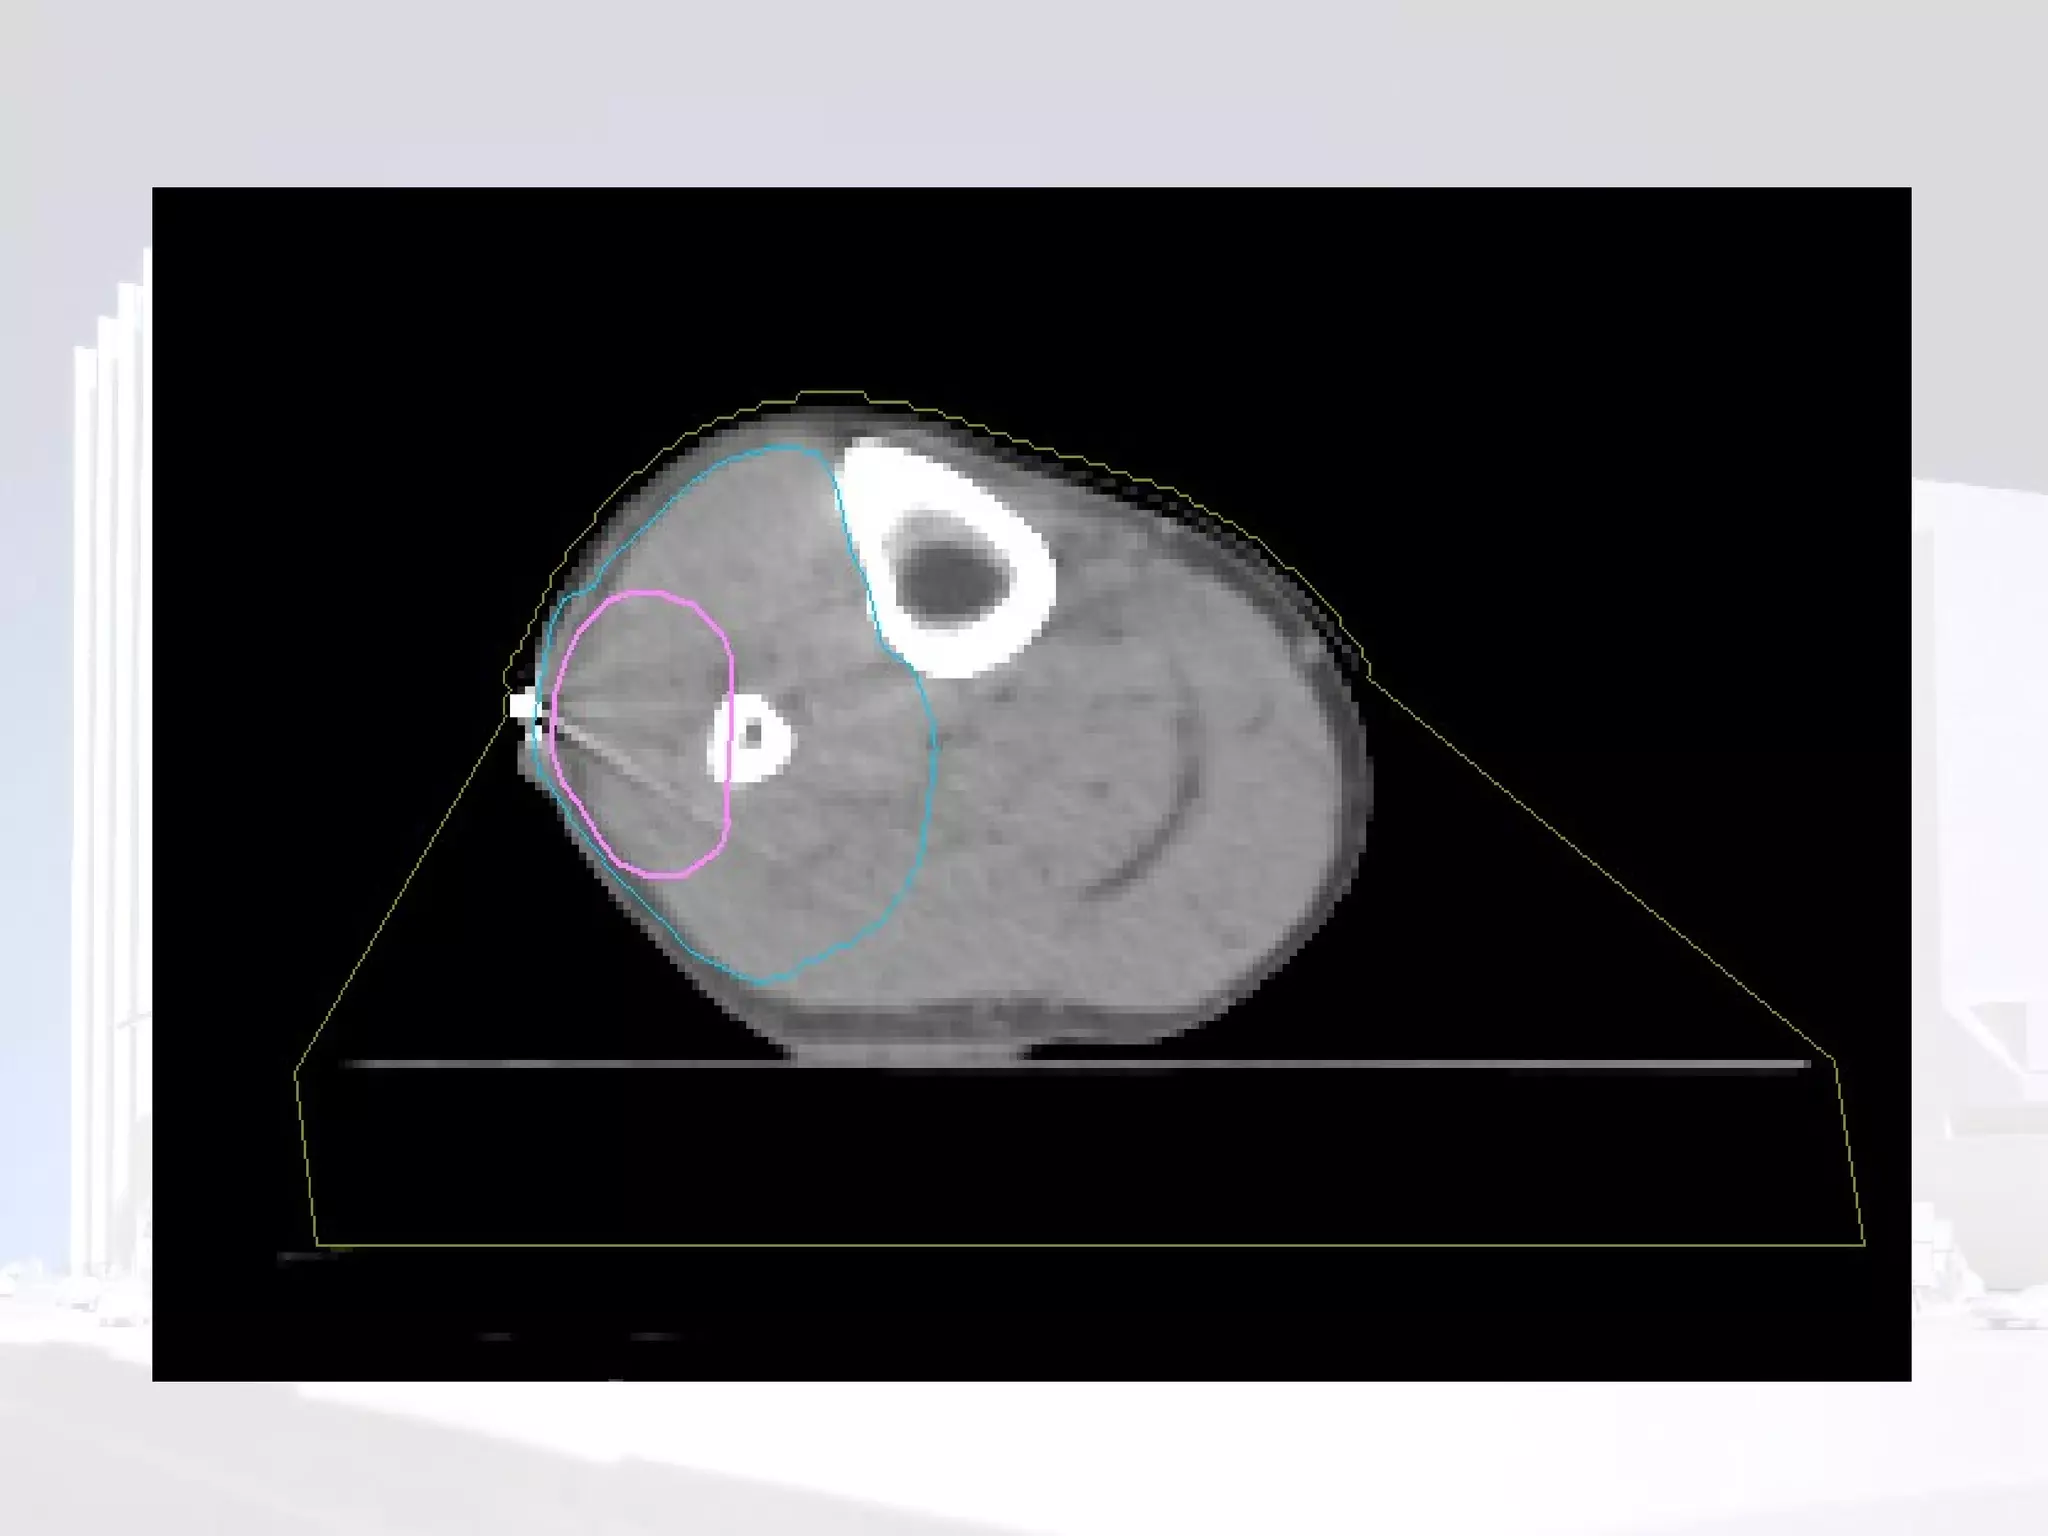

Planning

Phase I  Volume definition GTV  reconstructed from pre-op imaging. Consider compartment at risk of microscopic spread. Should include biopsy site and scar CTV  (length) =  GTV  + 4-9cm (usually ~5cm) PTV  =  CTV  + 5-10mm (depending on departmental set up) or 1 cm beyond scar  Trans-axial CTV -  treat width of compartment or  GTV  + 2-3cm

Sparing a “corridor” Leaving an area of normal tissue within the circumference of the limb can reduce risk of lymphoedema

Sparing a “corridor ” Leaving an area of normal tissue within the circumference of the limb can reduce risk of lymphoedema